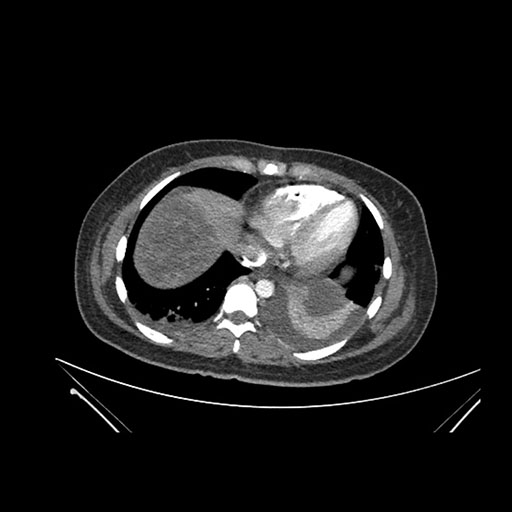

Axial Arterial

Axial Venous